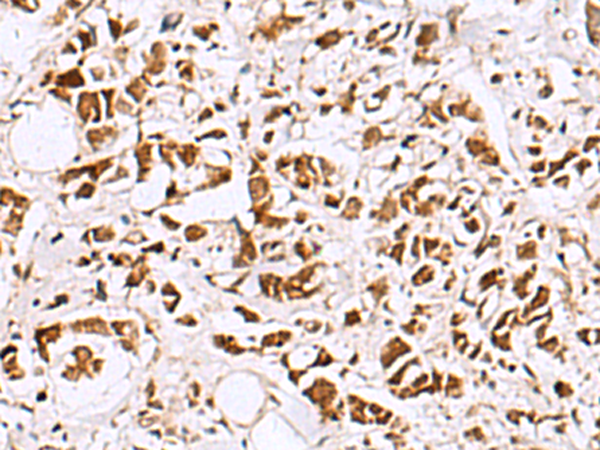

The image is immunohistochemistry of paraffin-embedded Human breast cancer tissue using (EWSR1 Antibody) at dilution 1/60. (Original magnification: ×200)